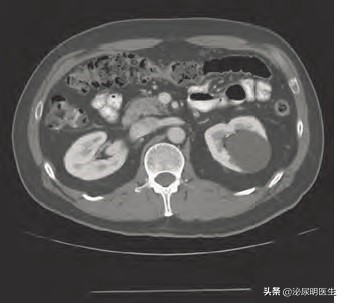

从影像学表现来看,B超肾囊肿表现是1、界限清楚的囊内无回声的空腔;2,囊壁光滑,囊液透声清楚,3、囊壁回声增强。符合这三条诊断的单纯性肾囊肿成立可能性95%. CT表现为囊壁薄,均值,边缘锐利整齐,CT值一般低于20,静脉注射造影剂后无强化表现。囊肿感染或出血或含高蛋白液体,CT值可升高。MRI一般用于对造影剂过敏或肾功能不全的患者,MRI有利于明确囊液性质,单纯性肾囊肿在T1加权上表现为低信号,在T2信号上表现为高信号(就是白色的)。

综上所述,单纯性肾囊肿和多囊肾的关系您看明白了吗?简单地说,如果B超CT上看到了肾囊肿之间有正常的肾实质一般认为是多发囊肿,而且个数即使是多发的,也会存在正常的肾实质,而多囊肾发病后则很难看到正常肾组织,且存在大大小小的囊肿,也就是说有大的、巨大的,中等的,小的,极小的,我们所说的囊肿爷爷、儿子、孙子、曾孙子都存在的病灶,而囊肿一般说来边界清楚,即时大小不一,也不像多囊肾那样密集恐惧症般的存在,在手术治疗和方法上更是明显不同,您看明白了吗?